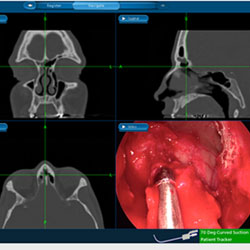

Endoscopic sinus surgery is a common procedure that is usually performed for patients with chronic sinusitis. Chronic sinusitis can dramatically affect a patient’s quality of life. Ninety percent of patients who have undergone sinus surgery…